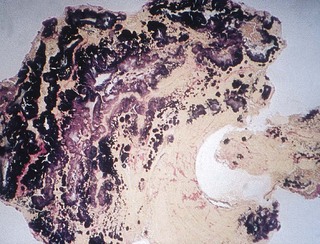

3. The next critical event occurs when organisms circulating in the blood (e.g. after a tooth extraction or scaling) attach to or become trapped in the thrombotic endocardium or the prosthetic device. The resultant platelet–fibrin–bacterial mass, now called the bacterial vegetation, constitutes the primary pathology of infective endocarditis (Figs 23.2 and 24.2).

image

Fig. 24.2 Micrograph of an infected heart valve teeming with Gram-positive streptococci.